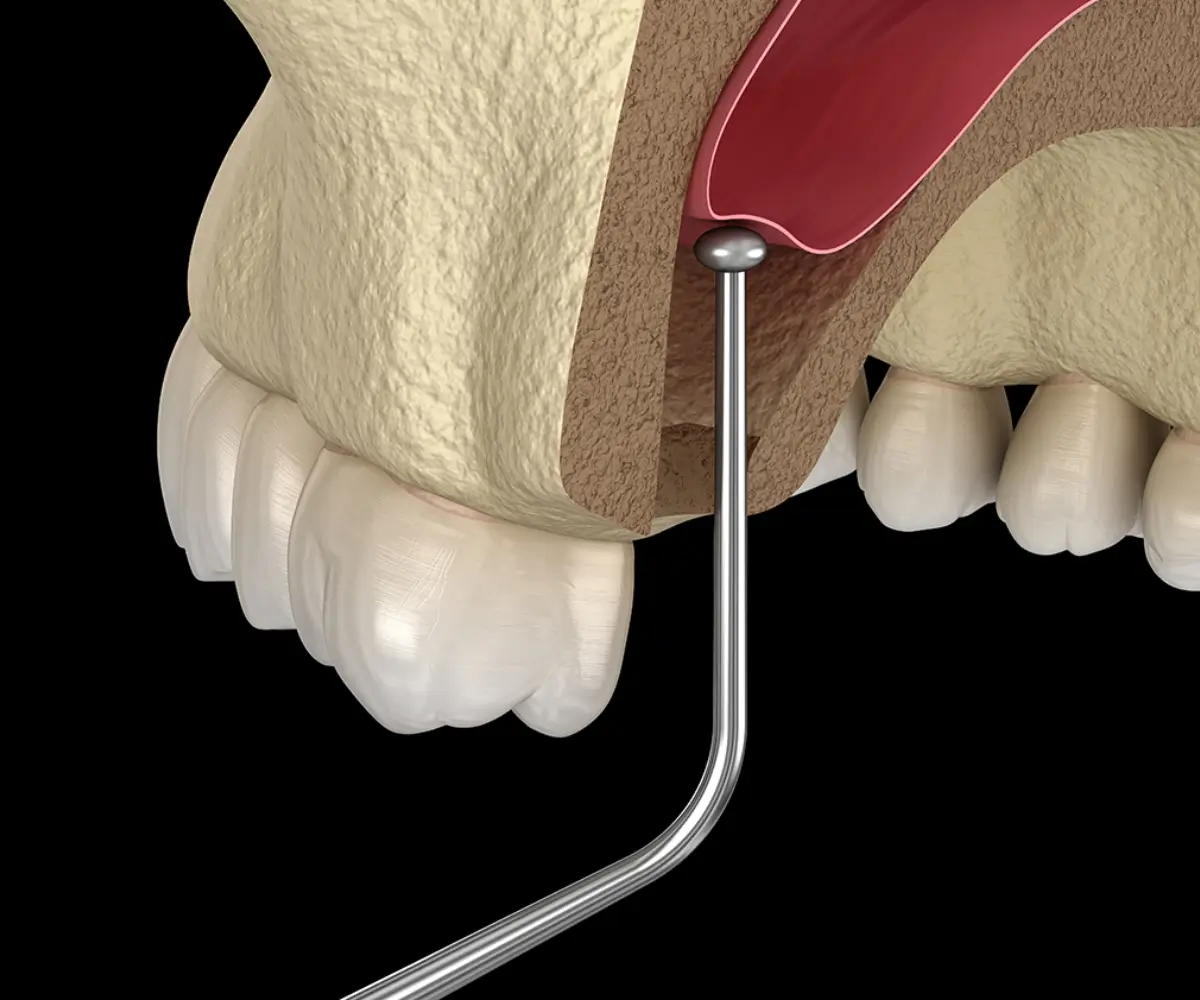

Bone grafting and sinus lift procedures help strengthen the jawbone and create a stable foundation for successful dental implant placement. These treatments are carefully planned to improve long-term implant stability and support lasting treatment outcomes.